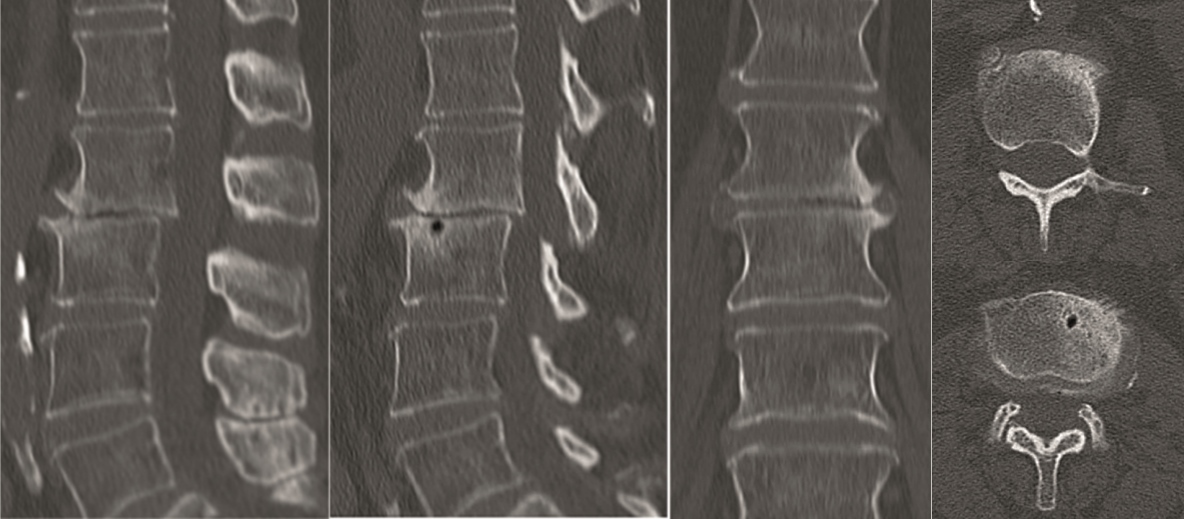

A 40-year-old man 5 years after ALIF L4-L5 using SynFix with axial low back pain. The CT scan shows locked pseudarthrosis (Fig 17). Nonoperative treatment failed. The treatment option was bilateral Facet Wedge at L4-L5.

A less invasive approach was used with Insight Retractor using the bilateral Facet Wedge. No bone graft. X-ray follow-up after 3 months and CT assessment after 6 months (Fig 18-19).